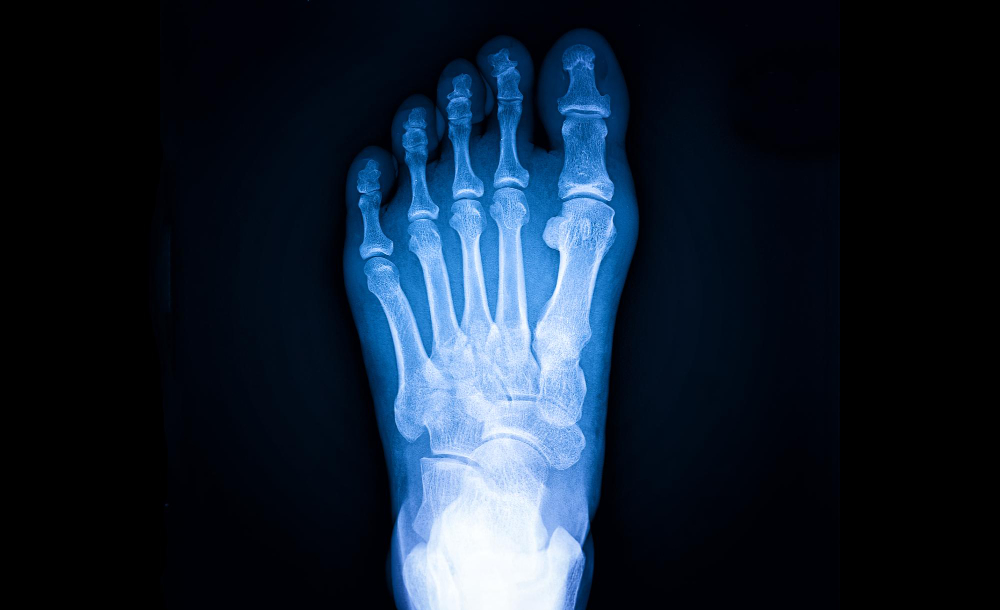

Artículo sobre Tratamiento del Neuroma de Morton ofrecido por Dr. Francisco Castillo Vazquez